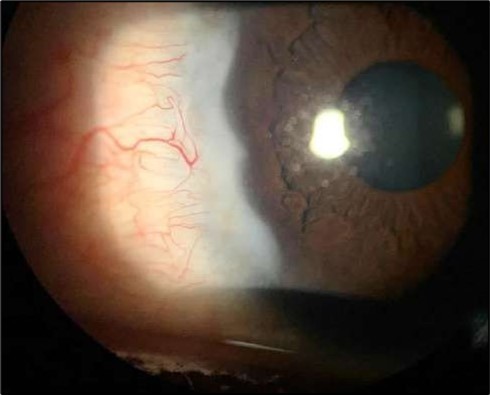

On the current presentation, Snellen VA was 6/6 in the right eye and 6/9 in the left eye, with normal IOP. The left eye demonstrated mild upper lid edema and intense nasal ciliary injection. Slit-lamp evaluation revealed a crescentic area of stromal corneal melting between 7 and 10 o’clock nasally, with overhanging edges and a fluorescein-positive base. No corneal infiltrates were present, and the surrounding stroma remained clear. The anterior chamber was deep and quiet, lens was transparent, pupil was round and reactive & normal posterior segment. Anterior segment optical coherence tomography (AS-OCT) confirmed a localized ulcer, measuring 1324 µm in horizontal width and extending to a depth of 380 μm, compared with an adjacent healthy corneal thickness of 824 µm, corresponding to approximately 46.1% stromal thinning (Figure 1a, Figure 1b, Figure 1c)

Figure 1a.Left eye (OS), on presentation. Slit-lamp image: crescent-shaped peripheral corneal ulceration located nasally, with severe adjacent conjunctival injection, peripheral thinning, and stromal infiltration.

Two weeks post-surgery, the left eye showed significant healing, with a small conjunctival granuloma and vascularization at the ulcer margins. The cornea was clear with a central leading edge nasally, deep and quiet anterior chamber and clear lens. VA 6/6 bilaterally and IOP normal. Histopathology of excised conjunctiva showed non-keratinized squamous epithelium with superficial erosions, stromal elastosis, hemorrhage, and inflammatory infiltration, but no signs of granulomatous disease, malignancy, or viral evidence, findings consistent with idiopathic localized inflammatory process. The patient reported significant relief and satisfaction post-surgery, resuming normal activities. Treatment continued with oral prednisolone 25 milligrams every other day, tobramycin-dexamethasone ointment twice daily, and preservative-free artificial tears four times daily Figure 4, Figure 5a, Figure 5b, Figure 5c, Figure 5d.

At six-months follow-up post-resection, the ulcer showed progressive epithelialization with no recurrence. Oral prednisolone was gradually tapered and stopped. The patient remains under regular ophthalmology follow-up with stable ocular findings Figure 6.

Figure 6.Six-month follow-up image showing a stable ocular surface, and absence of ulcer recurrence. The cornea appears clear centrally, with stromal scarring limited to the periphery.